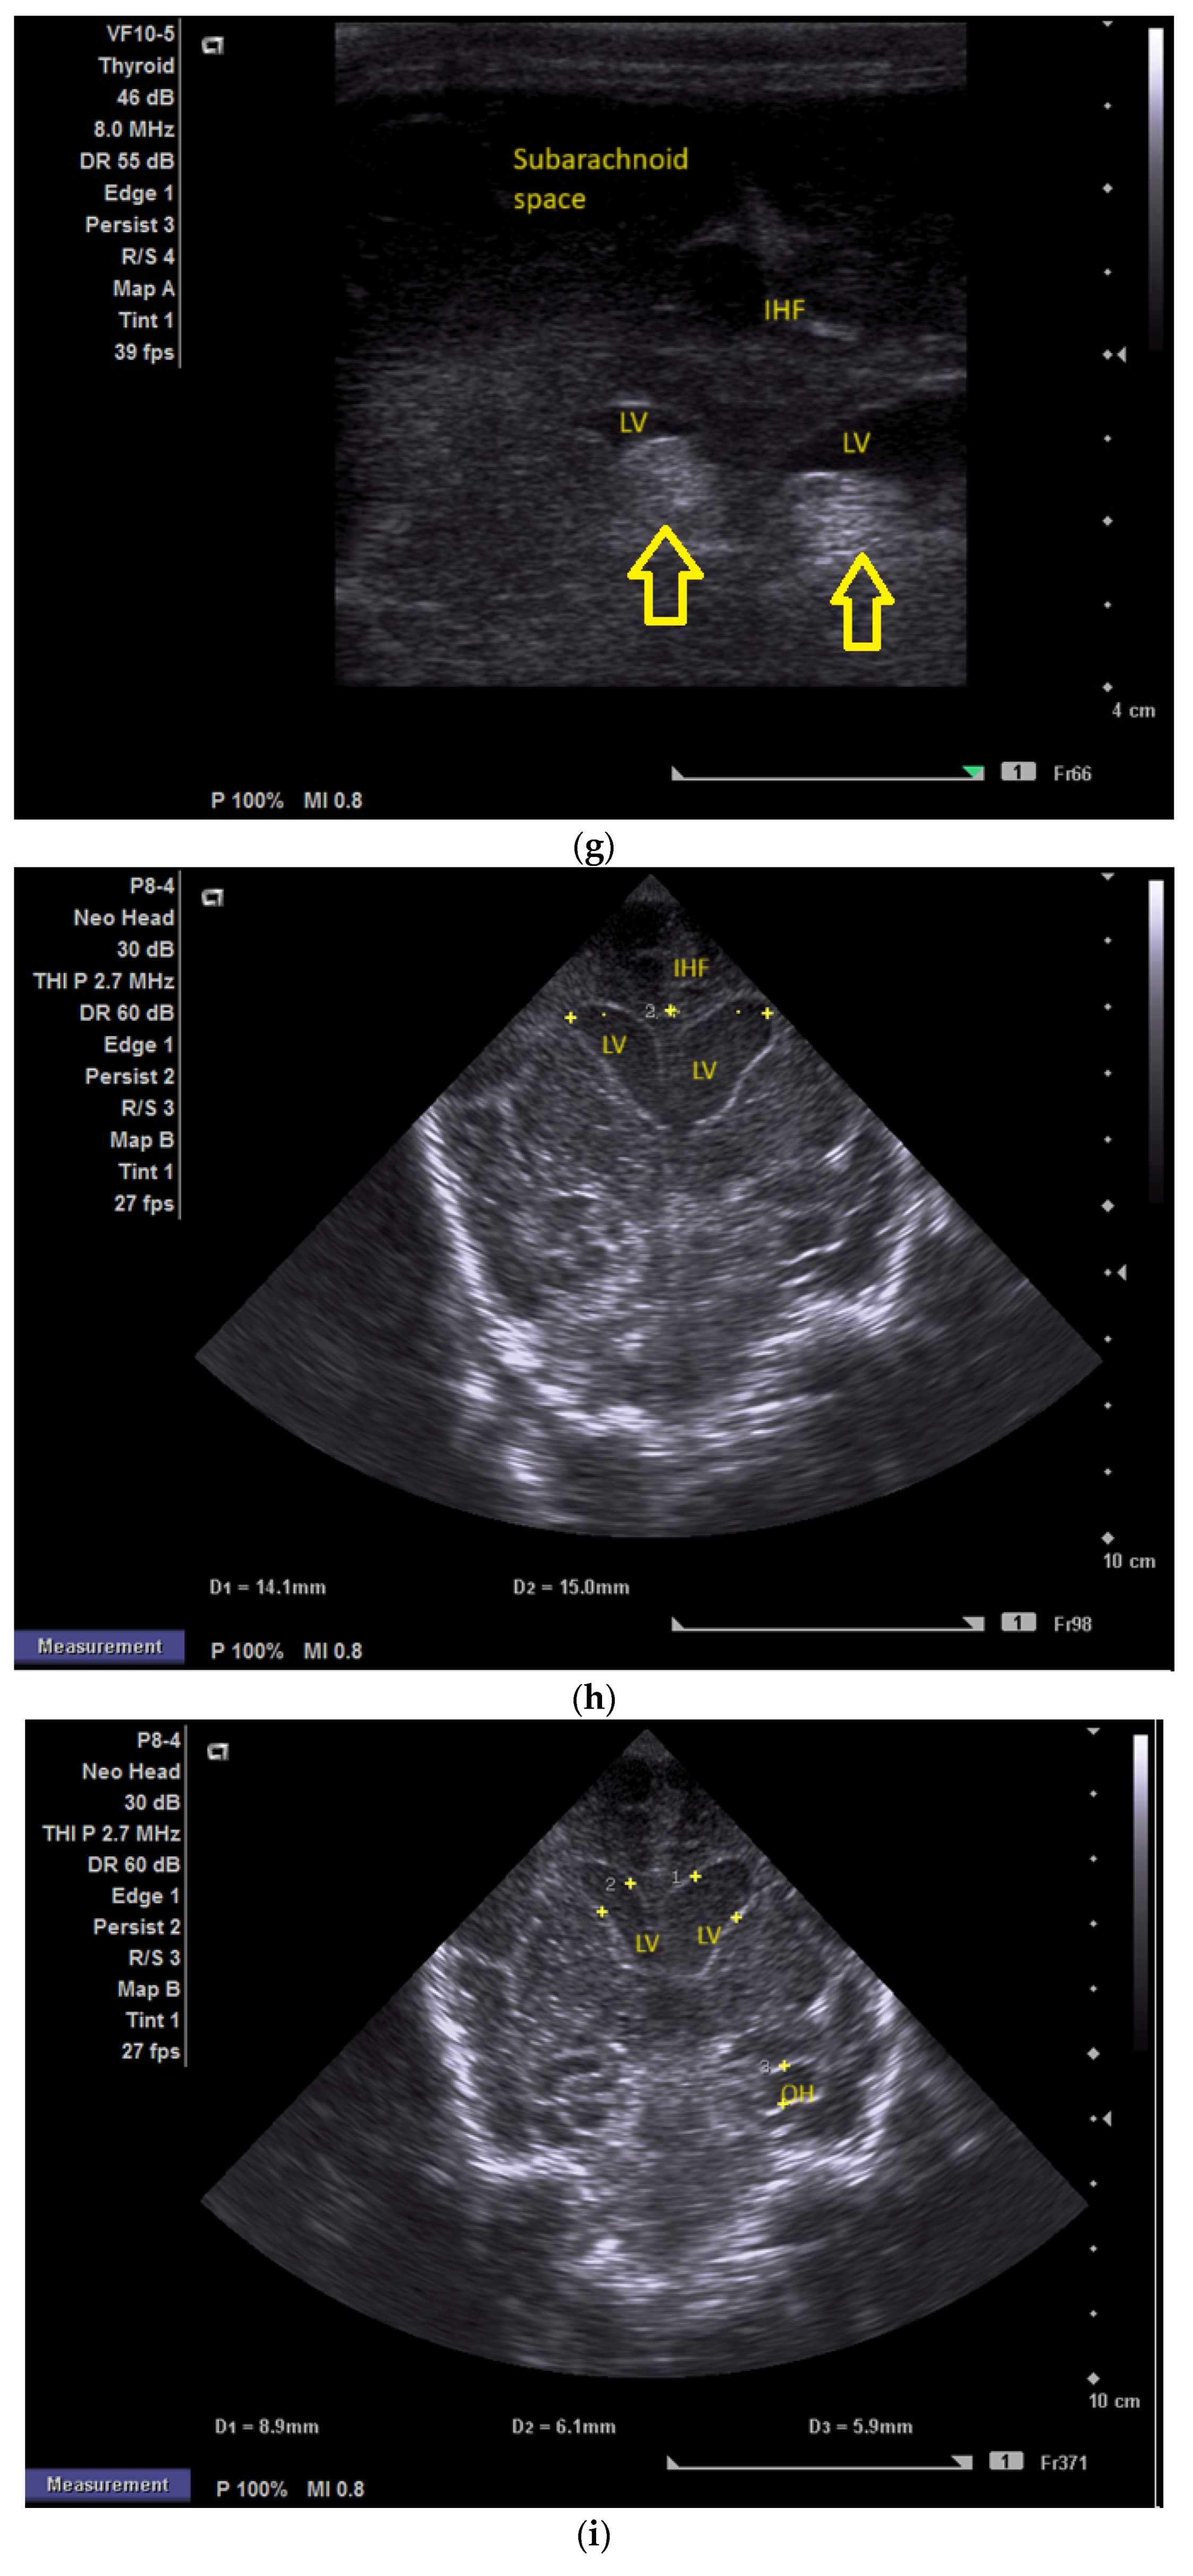

(a) Cranial ultrasound. Day one. Coronal view. D1 and D2—Levine index measurement. D3—cisterna magna measurement (personal image collection). (b) Cranial ultrasound. Day one. Coronal view. Lateral ventricle dilatation. LV—lateral ventricles. PC—plexus choroidus (personal image collection). (c) Cranial ultrasound. Day one. Right lateral ventricle. D1—thalamo-occipital distance measurement. Yellow arrow—parieto-occipital hyperechoic images (personal image collection). (d) Cranial ultrasound. Day one. Left lateral ventricle. D1—thalamo-occipital distance measurement. Yellow arrow—parieto-occipital hyperechoic images (personal image collection). (e) Day three. Cranial ultrasound. Coronal view. Ventricular asymmetry. D1 and D2—Levine index measurement. D3 and D4—anterior horn width measurement. Left ventricular enlargement (personal image collection). (f) Day three. Cranial ultrasound. Coronal view. Ventricular asymmetry (left ventricle larger than right ventricle). Yellow arrows—periventricular hyperechoic images are becoming more visible (personal image collection). (g) Day three. Cranial ultrasound. Coronal view. Linear probe. Ventricular asymmetry (left ventricle larger than right ventricle). LV—lateral ventricle (anterior horns). IHF—interhemispheric fissure. Yellow arrows—hyperechoic images in the thalamic-caudate groove (suggestive of a germinal matrix hemorrhage) (personal image collection). (h,i) Day 13. First LP. Cranial ultrasound. Coronal view. Up (before LP). D1 and D2—Levine index measurement. LV—lateral ventricles (anterior horns). IHF—interhemispheric fissure. Down (after LP). Dimensions of ventricles were reduced after LP. D1 and D2—anterior horn width. LV—lateral ventricles (anterior horns). OH—occipital horn (personal image collection). (j,k) Day 19. Second LP. Cranial ultrasound. Coronal view. Dimensions of ventricles were reduced after LP. Left (before LP). D1 and D2—Levine index measurement. Right (after LP). D1 and D2—Levine index measurement (personal image collection). (l) Day 39. Cranial ultrasound. Coronal view. Yellow arrows—periventricular cystic hyperechoic images—suggesting periventricular leukomalacia (cystic form) (personal image collection). (m) Head circumference-for-age. “X” symbols represent the measurements performed from birth and follow-up examinations. Initially, the head circumference was under the curve (personal image collection) [28].

After 72 h, the patient was extubated. The CUS showed bilateral IVH (grade III Volpe/Papile) (Figure 1e,f).

During the in-stay, two lumbar punctures (LP) were performed (Figure 1h–k).

In evolution, our patient presented bilateral ventricular dilatation and bilateral PVL (cystic form, grade III) (Figure 1l). The neurological assessment established eye contact and the infant could hold its head during the traction maneuver. The passive tone assessment showed the “scarf sign”, with the elbow at the midline bilaterally and a popliteal angle of 90°. The deep tendon reflexes (DTRs) were symmetrical.